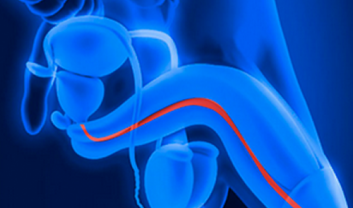

Urethral Stricture is a narrowing of the urethra, the tube that carries urine from the bladder out of the body. This constriction can lead to various...